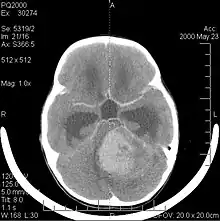

A tomografia computadorizada (TC) e a ressonância magnética (RM) podem detectar efetivamente uma neoplasia no cérebro. A RM é mais sensível que a TC para identificar lesões, mas contraindicações para pacientes com marcapasso cardíaco, próteses incompatíveis, clipes metálicos e outros. A TC continua sendo o método de escolha para detectar calcificações dentro de lesões ou erosões ósseas da calota craniana ou da base. A utilização de agentes de contraste, que são iodados no caso da TC e paramagnéticos ( gadolínio ) no caso da RM, permite a aquisição de informações sobre a vascularização e integridade da barreira hematoencefálica, uma melhor definição do tumor tumoral comparado ao edema circundante e à geração de hipóteses sobre o grau de malignidade . O exame radiológico também permite avaliar os efeitos mecânicos e consequentes alterações nas estruturas cerebrais decorrentes do tumor, como hidrocefalia e hérnias, cujos efeitos podem ser fatais. Finalmente, na preparação para a cirurgia, esse diagnóstico pode ser usado para determinar a localização da lesão ou a infiltração do tumor em áreas vitais do cérebro. Para isso, a RM é mais eficiente que a TC, pois pode fornecer imagens tridimensionais.

As ferramentas de diagnóstico por imagem radiológica destacam a mudança no tecido neoplásico em comparação com o parênquima cerebral normal (através de alterações na densidade do tecido fotografado eletronicamente na TC e na intensidade do sinal na RM). Como a maioria dos tecidos patológicos, os tumores também são reconhecidos por um acúmulo aumentado de água intracelular. Na tomografia computadorizada aparecem hipodensa, ou seja, de menor densidade que o parênquima cerebral, na tomografia de ressonância magnética nuclear com relaxamento spin-lattice T 1 hipointenso e em relaxamento spin-spin T 2 bem como a ponderação de prótons (PD) hiperintensa.

A tomografia computadorizada do cérebro normalmente mostra uma massa de tecido que pode ser realçada por qualquer contraste. Na TC, os gliomas de baixo grau geralmente parecem isodensos ao parênquima normal e, portanto, podem não apresentar realce pelo contraste. Da mesma forma, lesões na fossa posterior do crânio são difíceis de identificar na TC. Consequentemente, os resultados dessa tomografia isoladamente nem sempre são suficientes para fins diagnósticos. Em casos duvidosos, o uso da ressonância magnética mais sensível é essencial.